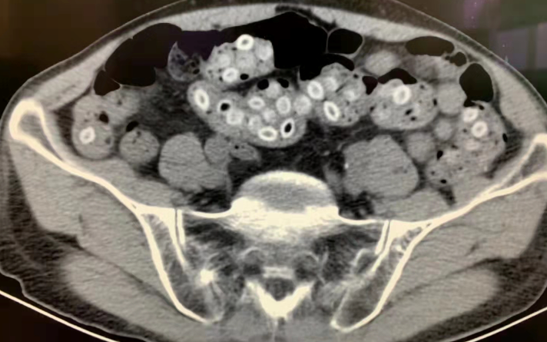

左下:吞入大量杨梅核引发肠梗阻